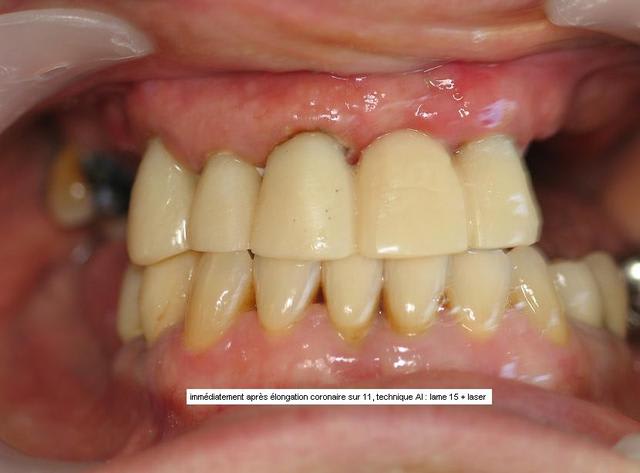

Un antre cas, pour faire plaisir à Jeff2 et montrer que le recentrage n'est pas systématique.

Après avoir fait ouvrir grand, bien relaxé la patiente, elle restait dévié en ouverture max, et fermait direct en dévié : donc, j'ai choisi de reconstruire sans recentrer. ( les recentrages et propulsions que j'ai pu réalisé en technique clausade, pourtant validé en posturo, ne m'ont jamais vraiment satisfait )

J'ai augmenté la DV pour retrouver une classe 1. Mais je ne sais pas si je vais pouvoir finir ainsi ou refaire une classe 3, car même si elle me dit que tout le monde la trouve changé en mieux, elle me dit a chaque RV, qu'elle a toujours eu le menton en avant, et que ce n'est pas possible de faire autrement !

De plus , le mari trouve les dents un peu longues et avancées, donc...